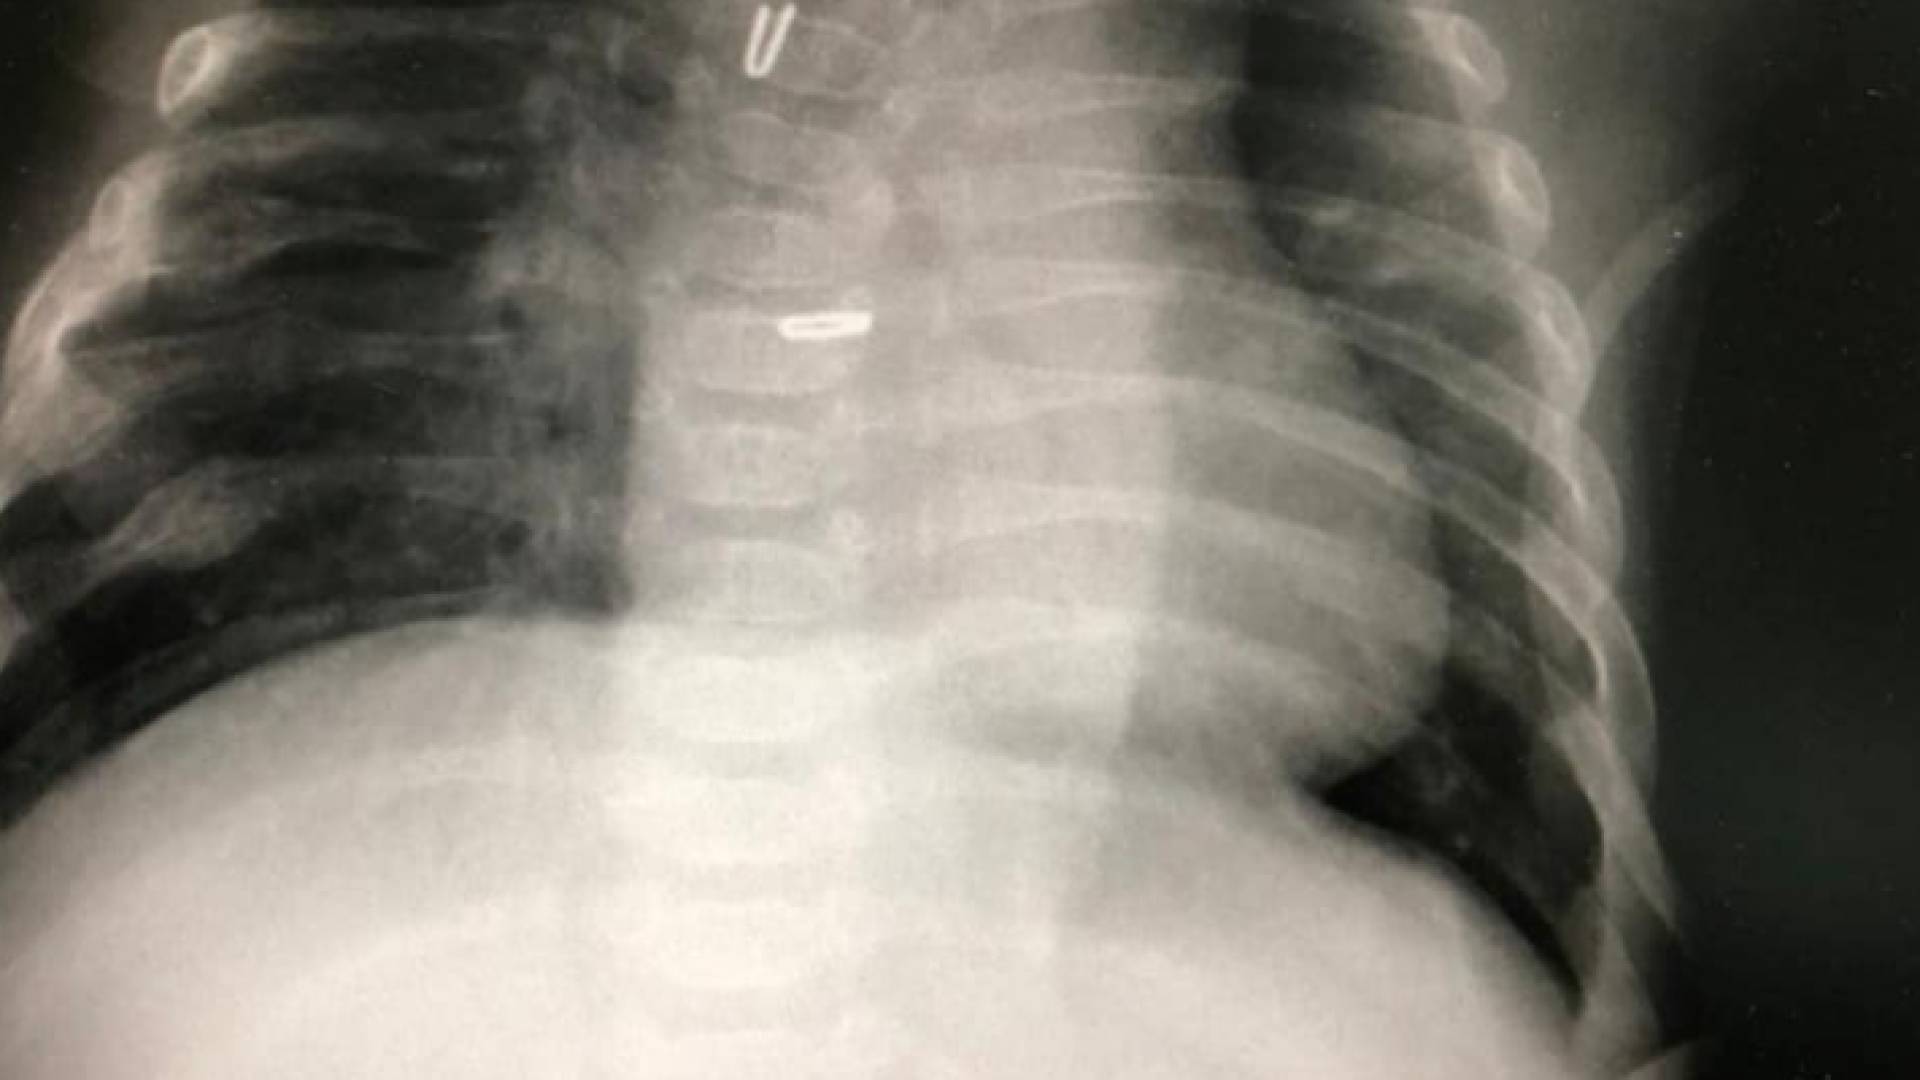

تمكن فريق طبي في جراحة الاطفال والتخدير وبمشاركة أطباء الأطفال والخداج في مستشفى الجامعة الاردنية، من إجراء عملية جراحية كبرى ونوعية لرضيع، رغم الظروف الصعبة وتحديات مواجهة جائحة كورونا؛ حيث تم إصلاح انسداد المريء الخلقي طويل البعد على مرحلتين.

وقال المستشفى في بيان الأحد، إن العملية تمت باستخدام المنظار الجراحي بالمرحلة الاولى، عندما كان عمر الطفل يومين، ومن ثم إجراء شد للطرف العلوي والسفلي للمريء داخل التجويف الصدري بتقنية حديثة، وتوصيل المريء بشكل طبيعي، بعد ستة أسابيع بنجاح، علما أن مثل هذه الحالات كانت تجرى سابقا عن طريق رفع المعدة كبديل عن المريء أو استخدام وصلة من القولون.